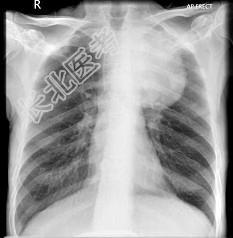

- 单项选择题56岁,男, 意识错乱情绪不稳定一周,请结合胸片和CT, 选出最可能的诊断 ( )

A、肺癌

B、错构瘤

C、胸内甲状腺肿

D、韦格肉芽肿

E、胸腺瘤